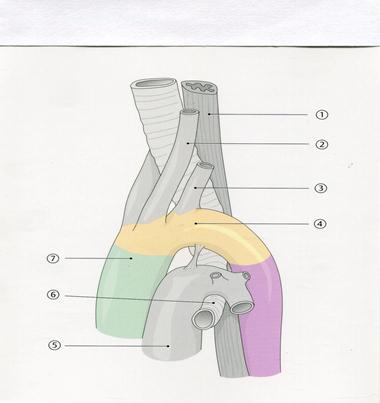

40. Төменде көрсетілген суреттегі белгіленген № 3 анатомиялық құрылымды атаңыз.

А. Айдаршықаралық шұңқырша

+Е. Ішкі ұйқы артериясы